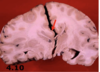

Parenchymal hemorrhage - pathology

The blood products are absorbed by macrophages and walled off by gliosis.

Months later, the cystic cavity appears tan - brown from hemosiderin-laden macrophages.